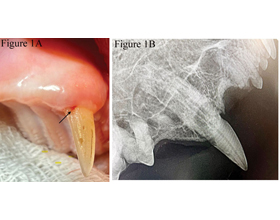

What’s all the chatter about?

Discover the fascinating phenomena behind jaw chattering in pets and learn about its common causes. Delve deeper into this important aspect of animal health.